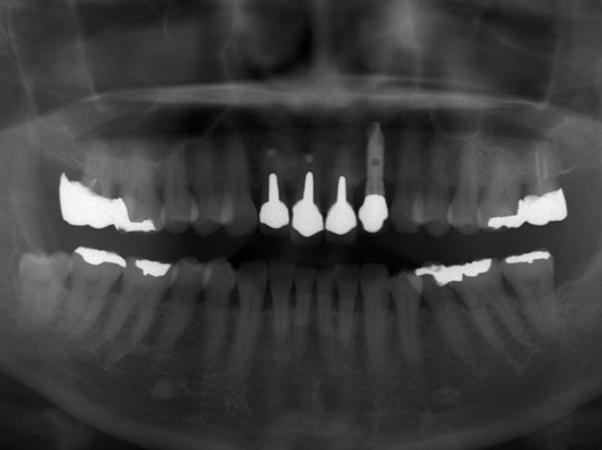

初診時パノラマレントゲン写真

右上1番と2番、左上1番の根の先には大きな病変(レントゲン上で黒く写っている部分)が確認できました。右上1番と2番に関しては、15年ほど前に歯根端切除を行っているとのことより、再手術を行うと現状よりもさらに歯根が短くなってしまい、歯の揺れが大きくなることが予想されました。